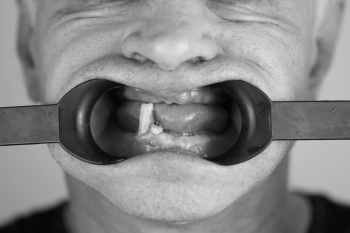

Родионов Артем Геннадьевич принимает в «Сеть стоматологических клиник ЭКСТРОДЕНТ» в Пушкине. Стаж 17 лет. Специализируется на хирургии и имплантологии, по которым клиника оказывает 16 услуг. Имеет 2 работы до/после в портфолио. Квалификация специалиста подтверждена 34 лицензиями, сертификатами и наградами.

2 работы в портфолио